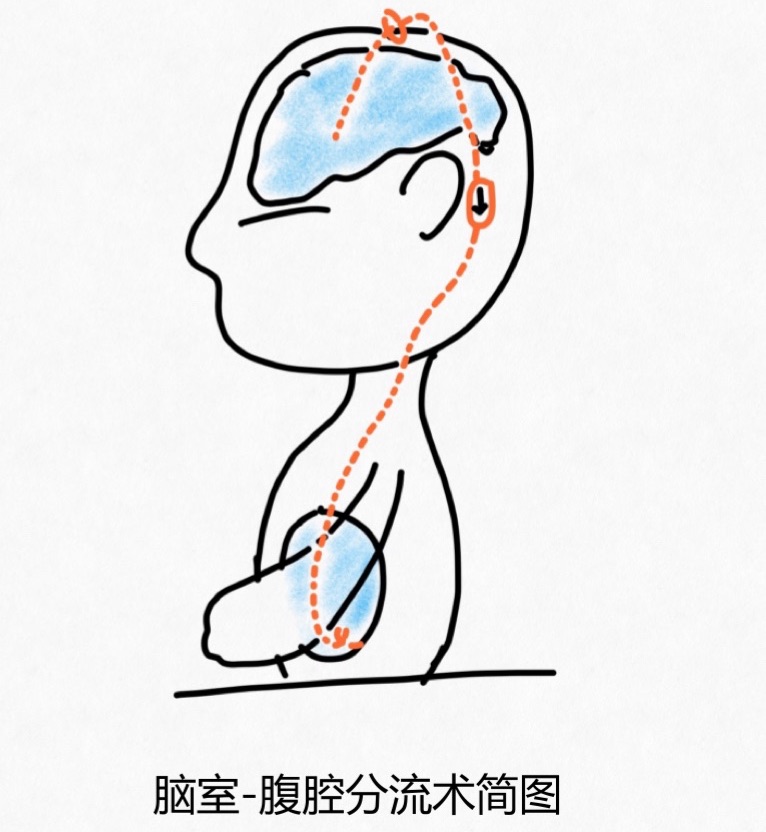

脑积水该怎么治疗? 脑积水是否需要治疗,需要专业的小儿神经外科医生评估后来决定方案。 1. 轻度脑积水:有部分宝宝在孕期即发现轻度侧脑室扩张,出生后检查也没有明显的进展,宝宝也没有异常的临床表现,那么就定期随访观察就可以了,一般不会影响宝宝的生长发育;部分年龄大的儿童,偶然间检查发现轻度脑积水,基本也是采取定期随访的方案,如果存在不明原因的头痛或者呕吐,不能认定其与脑积水明确相关,那么进行眼底检查评估是否存在脑积水相关的视乳头水肿,以上均无异常的情况下,这部分儿童也是定期随访就可以了。 2. 中-重度脑积水:对于中-重度的脑积水宝宝,只有一种治疗方案,就是手术治疗。采取什么样的手术治疗方案,需要小儿神经外科医生根据宝宝的年龄、症状以及脑积水的严重程度、病因等方面来选择制定的。手术的目的是进行脑脊液引流,减轻脑积水的程度及其对宝宝脑发育的影响。目前最常见的手术方式主要是脑室-腹腔分流术和神经内镜下第三脑室底造瘘术。简单的说,一种是靠管子把脑室里面的“水”引流到腹腔,让腹腔去吸收;另外一种也就是常说的微创手术,是在脑子里面、第三脑室底部打个洞,让脑室里面的“水”换条路走,让脑子自己去吸收,不需要放管子。所有需要手术的不同病因引起的脑积水都可以用脑室-腹腔分流术来解决问题,但三脑室造瘘手术并不适用于所有的脑积水宝宝,尤其年龄小于1岁的宝宝,失败率很高。所以,需不需要做手术、做什么手术,都需要小儿神经外科医生根据不同宝宝的情况来制定选择最适合她的方案。

脑室-腹腔分流术的简图

脑积水的治疗效果好吗? 脑积水的结局取决于它的病因、发病时间与持续时间、是不是有相应的结构异常、手术后有没有出现并发症,比如说感染、分流管故障等。大部分脑积水宝宝的治疗效果都是比较好的。脑积水是可以治疗的,而且早发现早治疗,更有利于挽救宝宝的神经发育结局,长期影响还是非常大的。 脑积水做了分流手术要终身带着管子吗?需要更换管子吗? 分流管毕竟是异物,而且也会出现故障或者感染,所以部分家长会有拿掉管子的想法,那么这种时候,小儿神经外科医生则会根据宝宝的脑积水恢复情况,通过调节阀门的压力、结扎管子停止引流的方法来尝试是否能够取掉管子。当分流管出现故障或者随着生长发育、管子不够长了,这时候就需要更换或者延长分流管。 脑积水宝宝手术出院后需要注意哪些呢? 手术治疗的脑积水宝宝需要接受长期神经外科随访,一般术后3个月要进行影像学检查评估脑积水改善的情况以及脑室扩张的程度,放管子的宝宝根据复查的结果决定是否需要调节阀门的压力,让脑子里面的“水”流的快一点或者慢一点。做造瘘的宝宝则需要评估造瘘口是不是通畅,是否需要改成分流手术。只要随访影像学检查提示脑室大小稳定、父母或者监护人能够熟练的观察判断宝宝的表现是否正常,就可以将随访的间隔延长。 经过小儿神经外科医生仔细的评估,多多脑积水比较严重,年龄小,不适合三脑室造瘘,所以采用脑室-腹腔分流术进行治疗,手术过程很顺利,术后恢复也比较好,术后3个月复查脑积水比之前有好转了,目前他抬头的时间比之前延长了,坐着也比之前稳当了,看着多多的进步,家里人终于是稍微松了一口气,不过医生也交代了,这是一个长期的过程,需要定期规律随访。